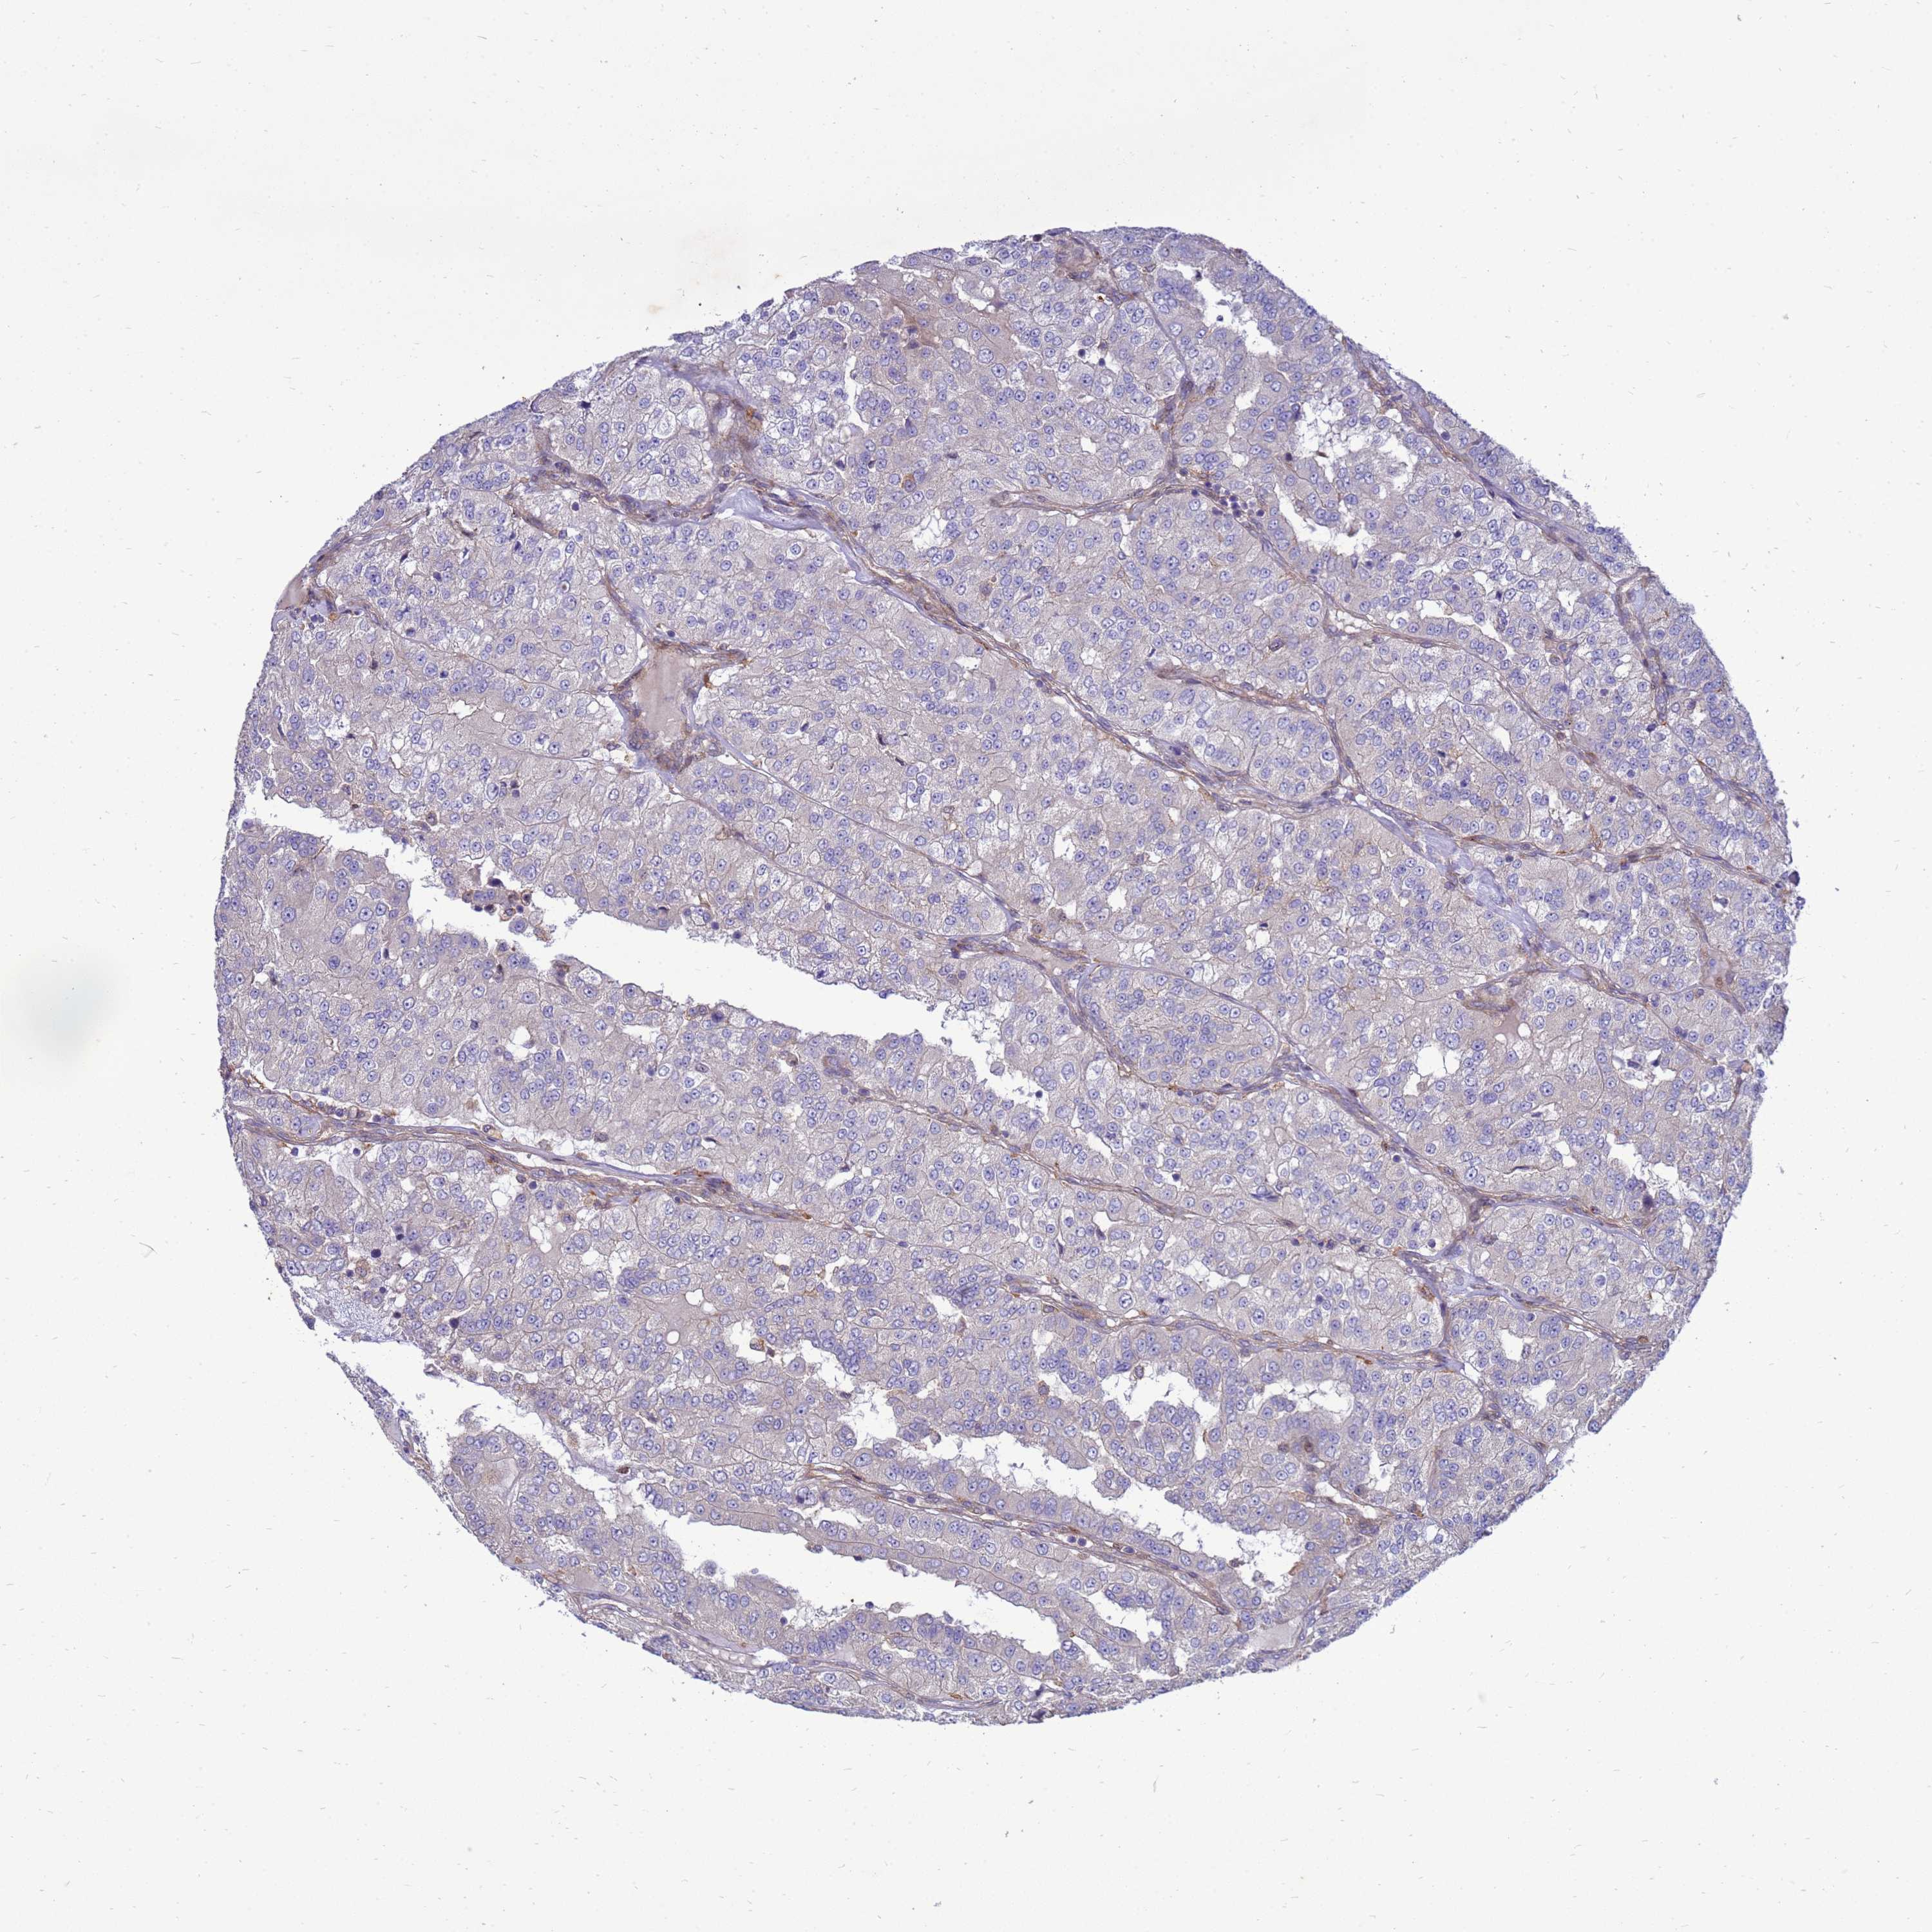

KIDNEY RENAL CLEAR CELL CARCINOMA (VALIDATION) - Interactive survival scatter ploti

The Survival Scatter plot shows the clinical status (i.e. dead or alive) for all individuals in the patient cohort, based on the same data that underlies the corresponding Kaplan-Meier plots. Patients that are alive at last time for follow-up are shown in blue and patients who have died during the study are shown in red.

The x-axis shows the expression levels (FPKM) of the investigated gene in the tumor tissue at the time of diagnosis. The y-axis shows the follow-up time after diagnosis (years). Both axes are complimented with kernel density curves demonstrating the data density over the axes. The top density plot shows the expression levels (FPKM) distribution among dead (red) and alive patients (blue). The right density plot shows the data density of the survived years of dead patients with high and low expression levels respectively, stratified using the cutoff indicated by the vertical dashed line through the Survival Scatter plot. This cutoff is automatically defined based on the FPKM cutoff that minimizes the p-score. The cutoff can be changed by dragging the vertical line or by entering a cutoff value in the square labeled "Current cut-off".

Under the Survival Scatter plot the p-score landscape (black curve; left axis) is shown together with dead median separation (red curve; right axis). Dead median separation is the difference in median mRNA expression between patients who have died with high and low expression, respectively. It is calculated as follows: median FPKM expression of dead patients with high expression - median FPKM expression of dead patients with low expression. This is intended to aid the user in visually exploring custom cutoffs and the associated p-scores and dead median separation.

& Survival analysisi

Kaplan-Meier plots summarize results from analysis of correlation between mRNA expression level and patient survival. Patients were divided based on level of expression into one of the two groups "low" (under cut off) or "high" (over cut off). X-axis shows time for survival (years) and y-axis shows the probability of survival, where 1.0 corresponds to 100 percent.

RNF215 is not prognostic in Kidney Renal Clear Cell Carcinoma (validation)

Best expression cut offi

: 23.46

P scorei

N/A

Average pTPM 19.8

Number of samples 100